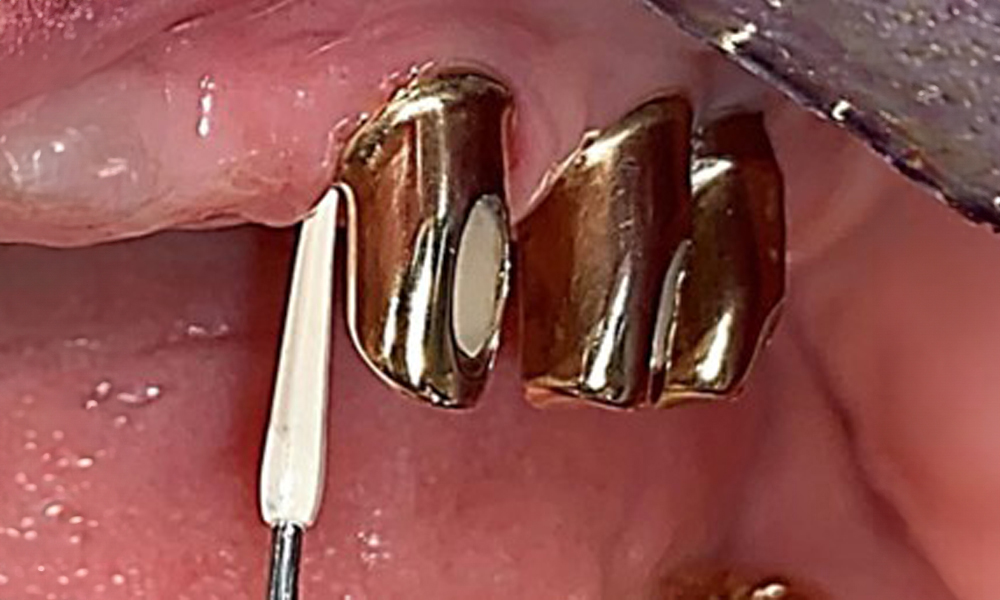

Probing implant 23 at a probing depth of 4 mm using a plastic probe, showing negative BOP findings and a hyperplastic papilla.

Fig. 6: Probing implant 23 at a probing depth of 4 mm using a plastic probe, showing negative BOP findings and a hyperplastic papilla.

The periodontal status should be thoroughly examined once a year. This examination provides comprehensive documentation of the periodontal and implant findings, including pocket depths, periodontal recession and furcation involvement. This will ensure a rapid response to any potential progression of the mucositis, gingivitis, periodontitis or peri-implantitis. Implant probing using a plastic probe is recommended. In the present case, a mesial probing depth of 4 mm was detected mesial to implant 23. No suppuration or bleeding was detected, indicating the absence of peri-implantitis.